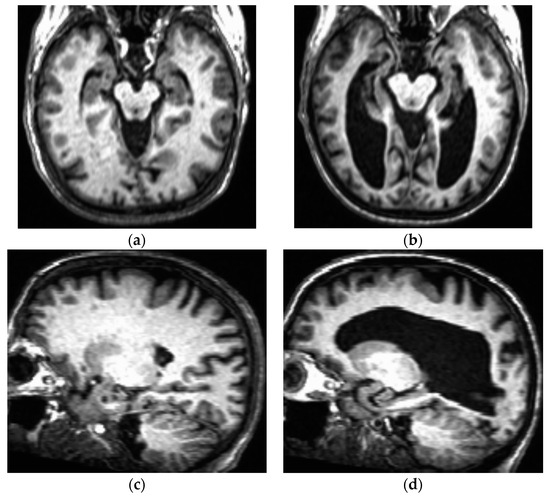

The possibility that anti-Aβ therapy may accelerate brain atrophy is yet another area of concern for the use of this therapeutic class in those with DSAD. This is particularly true because, in general, brains of individuals with DS (even in the absence of AD pathology) are already typically significantly smaller than those of age- and sex-matched peers without DS [97], with a disproportionate volume reductions in the frontal and temporal lobes and cerebellum [98]. In addition, people with DS tend to show accelerated brain aging [99], with their frontal, temporal, and parietal lobes showing greater age-related volume reduction than those of people without DS [100]. Furthermore, brain atrophy associated with DS can be greatly exacerbated by DSAD (see Figure 2 for an example of this phenomenon), with those with DSAD having a 19% lower mean brain weight than those with sporadic AD [101]. Morphometric MRI analyses have associated specific brain regions impacted by DSAD with detectable grey matter changes prior to signs of clinical dementia [102]. These grey matter volume reductions are typically detectable by MRI after amyloid accumulation has already occurred [84], which can actually be considered evidence in favor of the amyloid hypothesis for DSAD.

Figure 2.

T1-weighted anatomical 3-Tesla MRI images taken from two females with DS, both in the sixth decade of life (generously shared by Dr. Katherine Koenig). One of these individuals (MRIs depicted in panels (a,c)) did not show signs and symptoms of cognitive decline, whereas the other individual (b,d) had a formal diagnosis of DSAD at the time of the brain scan. (a) Axial section showing expected degrees of neocortical atrophy and lateral ventricular dilation for an older adult with DS; (b) Axial section taken at approximately the same anatomical plan as panel a, showing extensive neocortical atrophy and ventriculomegaly indicative of DSAD; (c,d) Sagittal views from the same individuals taken in the same MRI sessions shown in panels a and b, respectively.